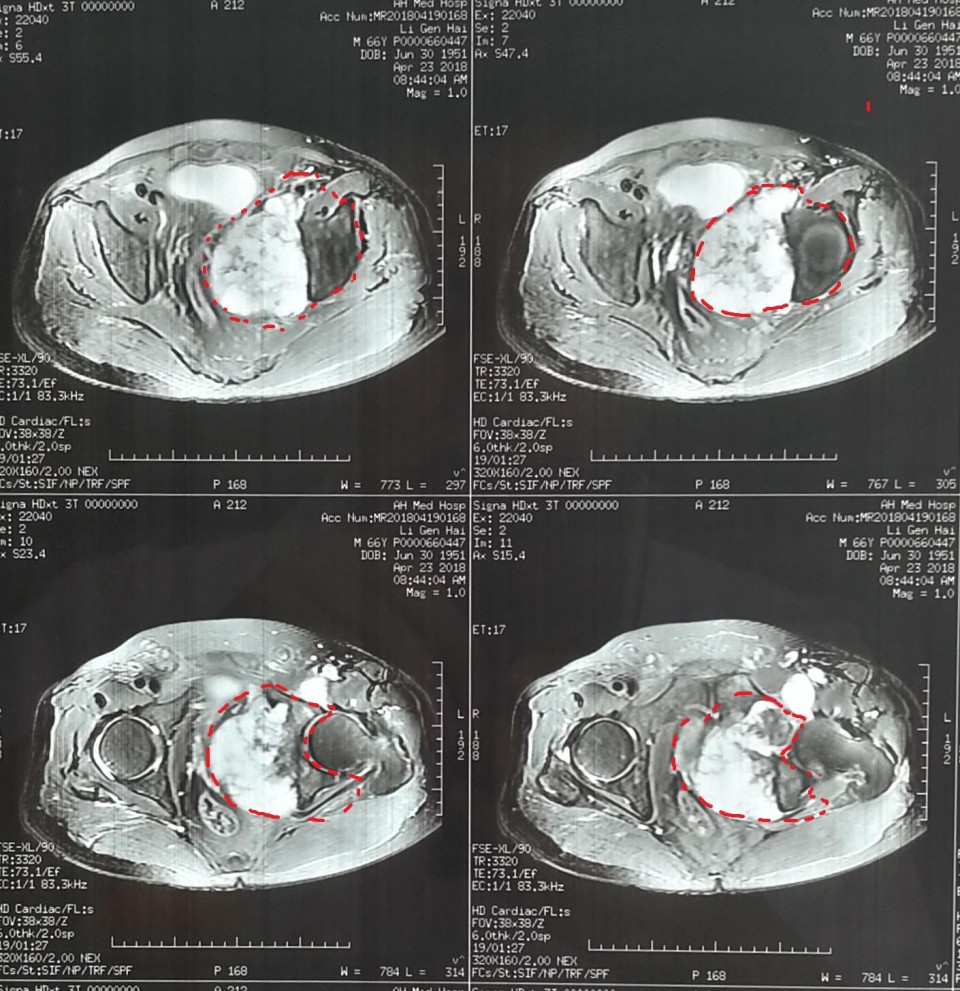

日前,骨病骨肿瘤科近日完成 “骨盆Ⅱ+Ⅲ区巨大软骨肉瘤行内半骨盆切除+股骨头旷置术的保肢治疗 ”1例。患者66岁男性,髋部疼痛不适3月余入院,经检查提示骨盆Ⅱ+Ⅲ区巨大恶性骨肿瘤。骨盆的恶性肿瘤,往往就诊时肿瘤已经发展了相当长的时间,而肿瘤巨大、术中出血多、局部解剖结构复杂等因素使得手术难度及风险增高。早年对骨盆恶性肿瘤的治疗,半骨盆截肢术是骨盆恶性肿瘤的主要治疗方式。但患者所承受的心理压力巨大,面对肢体残缺所引起的恐慌使其拒绝接受治疗,尤其对于年轻患者。保肢术的开展及应用为这些患者带来希望,但手术难度极大,不易达到安全的外科边界。胡勇教授团队根据患者病情,制定精细手术方案,多套手术预案,由于患者经济条件不佳,使用人工关节假体会造成患者极大负担,而且如果出现并发症需要治疗,更导致花费巨大。采用内半骨盆切除+股骨头旷置术,术中既完整的切除了肿瘤,又保全了半侧肢体,辅助术后功能锻炼,几乎可以达到与人工假体相媲美的肢体功能。患者术后顺利康复出院。

胡勇教授指出,骨盆肿瘤的规范化治疗中,肿瘤的完整切除在其治疗中占重要地位,由于骨盆位置深在,血管神经、肠道泌尿道毗邻,骨盆肿瘤的完整切除手术难度极大,技术要求高。对于肢体的重建,虽然人工假体并发症多、价格高昂,但能提供患者相对较好的髋关节功能,肢体长度和外形较满意,故对于大多数患者来说,只要局部软组织重建条件允许骨盆人工关节置换仍是首先考虑的重建方法。该患者由于经济原因不能承受人工假体高昂的费用支出,我们手术尽量保留髋臼顶部骨量,将股骨头置于该处,后期形成假关节可替代原髋关节保留行走功能。一些学者经过长期随访研究,认为旷置成形术避免了很多严重并发症,而且创建了一个无痛且有中等程度功能的肢体。类似骨盆肿瘤的手术我科已开展多例,均取得良好疗效。